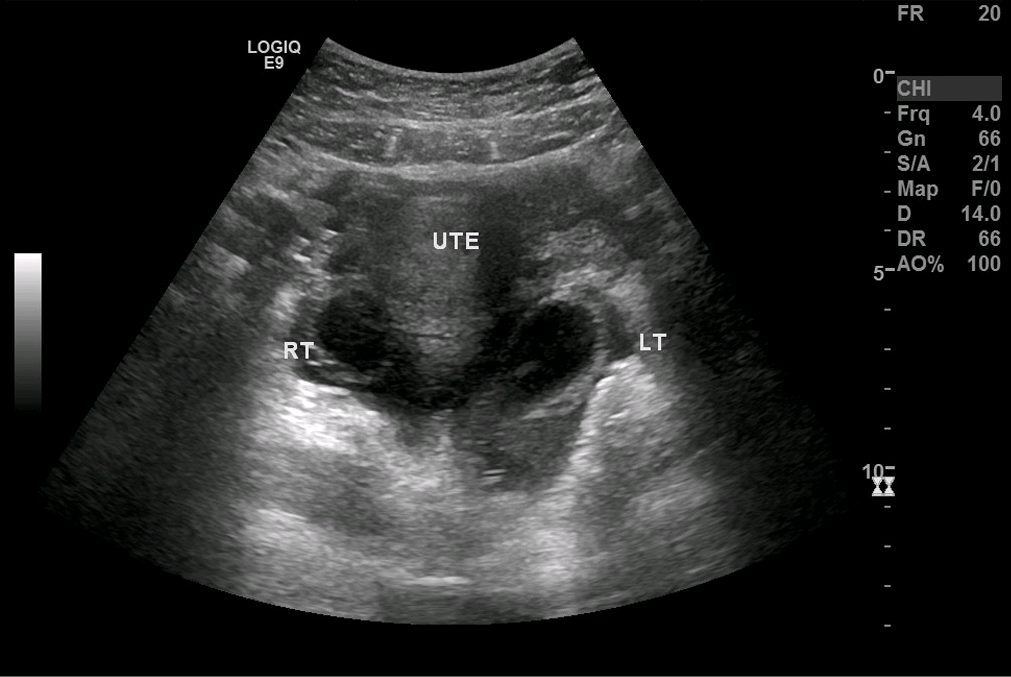

A tortuous tubular structure in the left adnexa raised suspicion for an isolated fallopian tube torsion (Figure 1). Results of an abdominal pelvic computed tomography scan confirmed a diagnosis of left fallopian tube torsion (Figure 2). The abnormal tubular structure was again visualized in the left adnexal region. The tubular diameter measured almost 2 cm. There was free fluid in the pelvis that was seen physiologically.